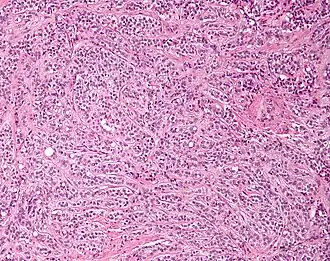

Micrograph of a Sertoli cell tumour. H&E stain. | |

A Sertoli cell tumour, also Sertoli cell tumor (US spelling), is a sex cord–gonadal stromal tumour of Sertoli cells. They can occur in the testis or ovary. They are very rare and generally peak between the ages of 35 and 50. They are typically well-differentiated and may be misdiagnosed as seminomas as they often appear very similar.[1]

Microscopy and immunohistochemistry are the only way to give a definitive diagnosis, especially when there is a suspected seminoma.[3]